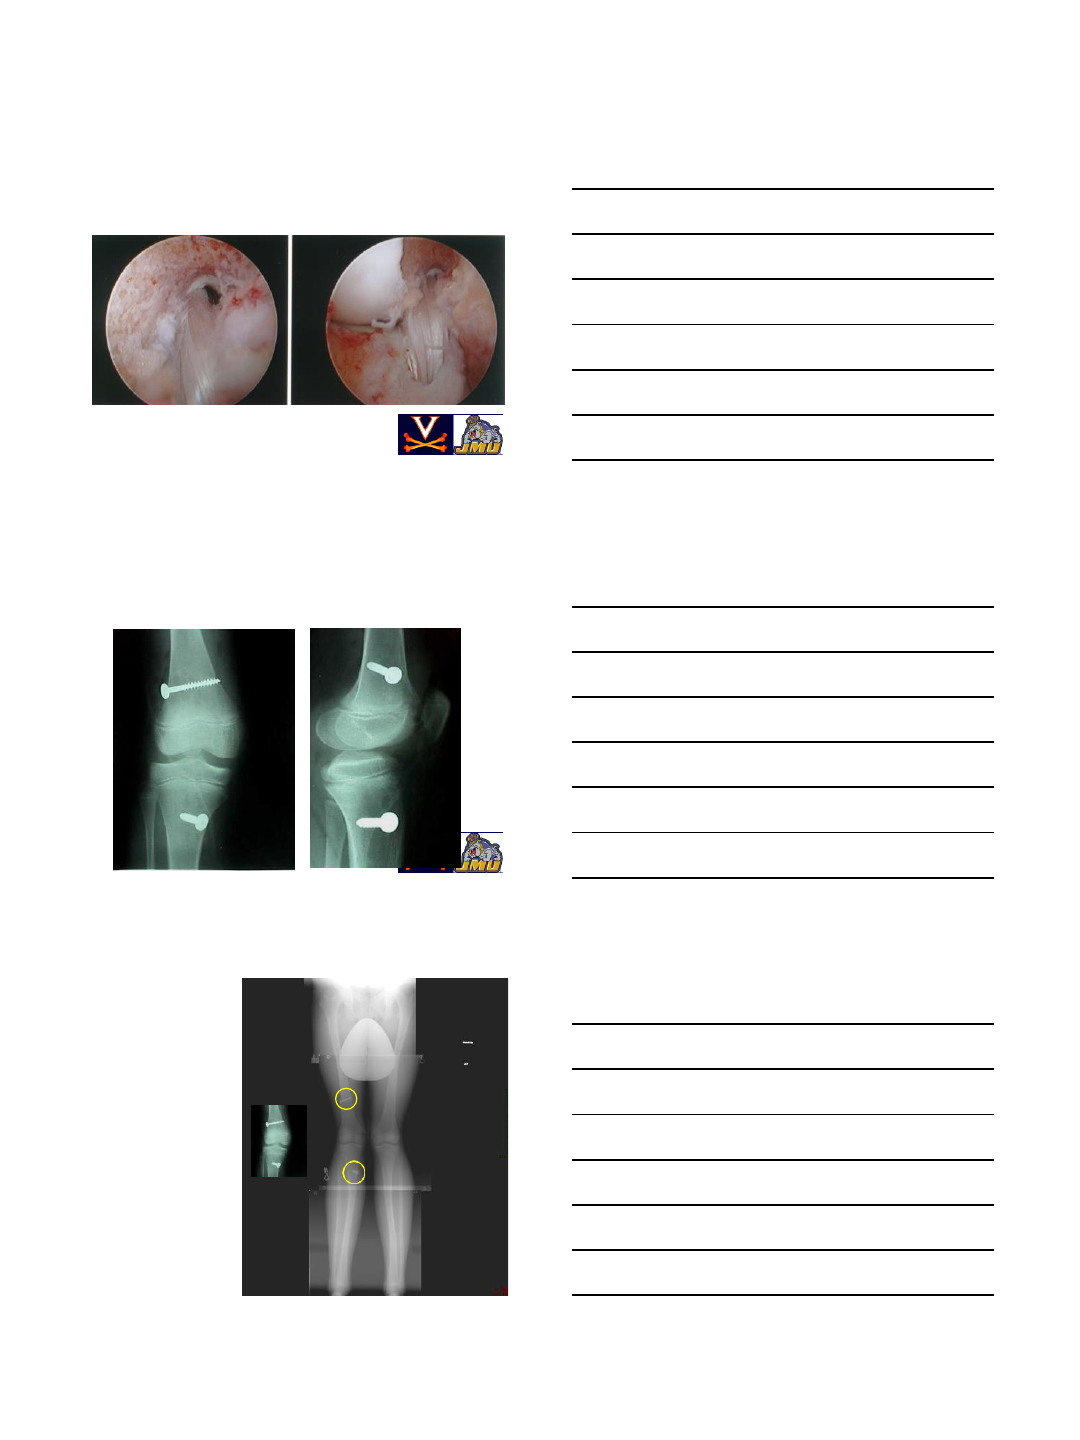

Removal of Loose Body

Lateral Meniscus Tear

Chondral Defect

ACL Graft

OATS Plugs